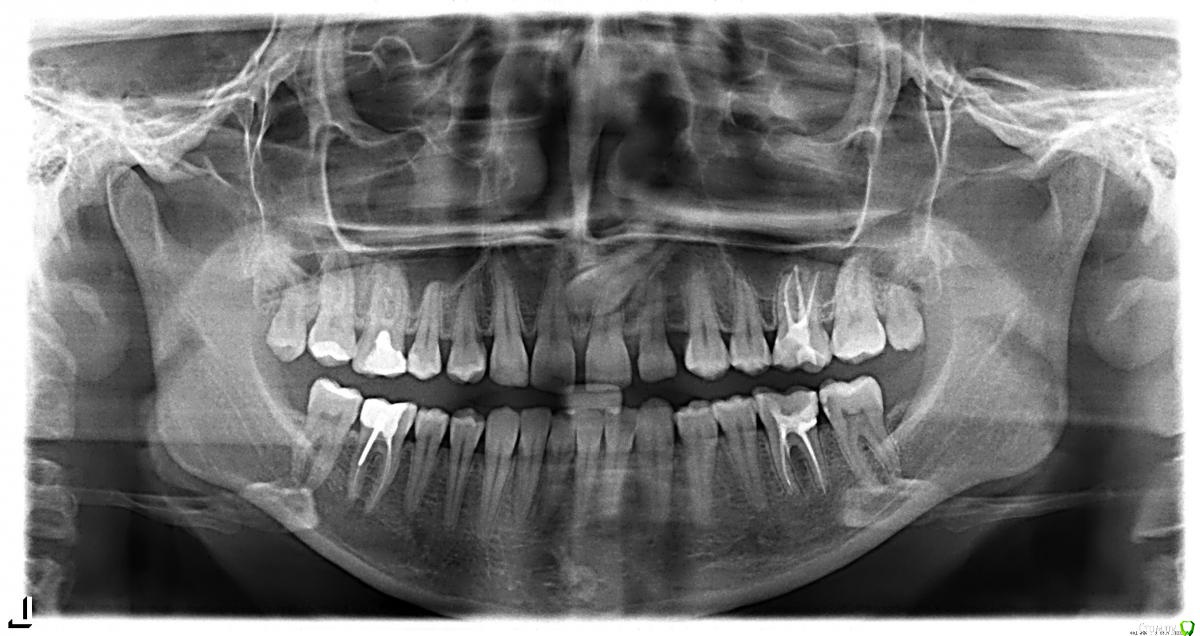

Jason Fa Опубликовано 1 мая, 2015 Поделиться Опубликовано 1 мая, 2015 Здравствуйте! Мне 23 года. Я планирую ортодонтическое лечение. С рождения у меня адентия резца 2.2. Клык встал на его место. Был недоразвит и его нарастили под резец около 7 лет назад. На правой стороне был ретенированный клык 1.3, который я приняла решение удалить и удалила (о чем сейчас жалею. Операция прошла крайне неудачно). То есть сейчас эстетически у меня нет обоих клыков на верхней челюсти. И щели между зубами. Рассматриваю два варианта:1. Открытие промежутков и импланты2. Закрыть промежуткиБыла на консультации у 3 ортодонтов. Все три предложили закрывать промежутки. Хотела бы уточнить как лучше быть. Прилагаю ТРГ и панорамный снимок. Панорамный снимок сделала в марте. До удаления клыка. ТРГ сделано позавчера. Сейчас нахожусь в стадии лечения 6рок и мелких кариесов. Знаю, что на закрытие должны быть определенные показания: гнатическое соотношение, профиль, контакты зубов. Хотелось бы понимать как изменится челюсть, профиль, форма губ, подбородка при таком закрытие. Буду благодарна за ответы! Заранее спасибо! Ссылка на комментарий

Jason Fa Опубликовано 6 мая, 2015 Автор Поделиться Опубликовано 6 мая, 2015 Вот как лежал клык Ссылка на комментарий